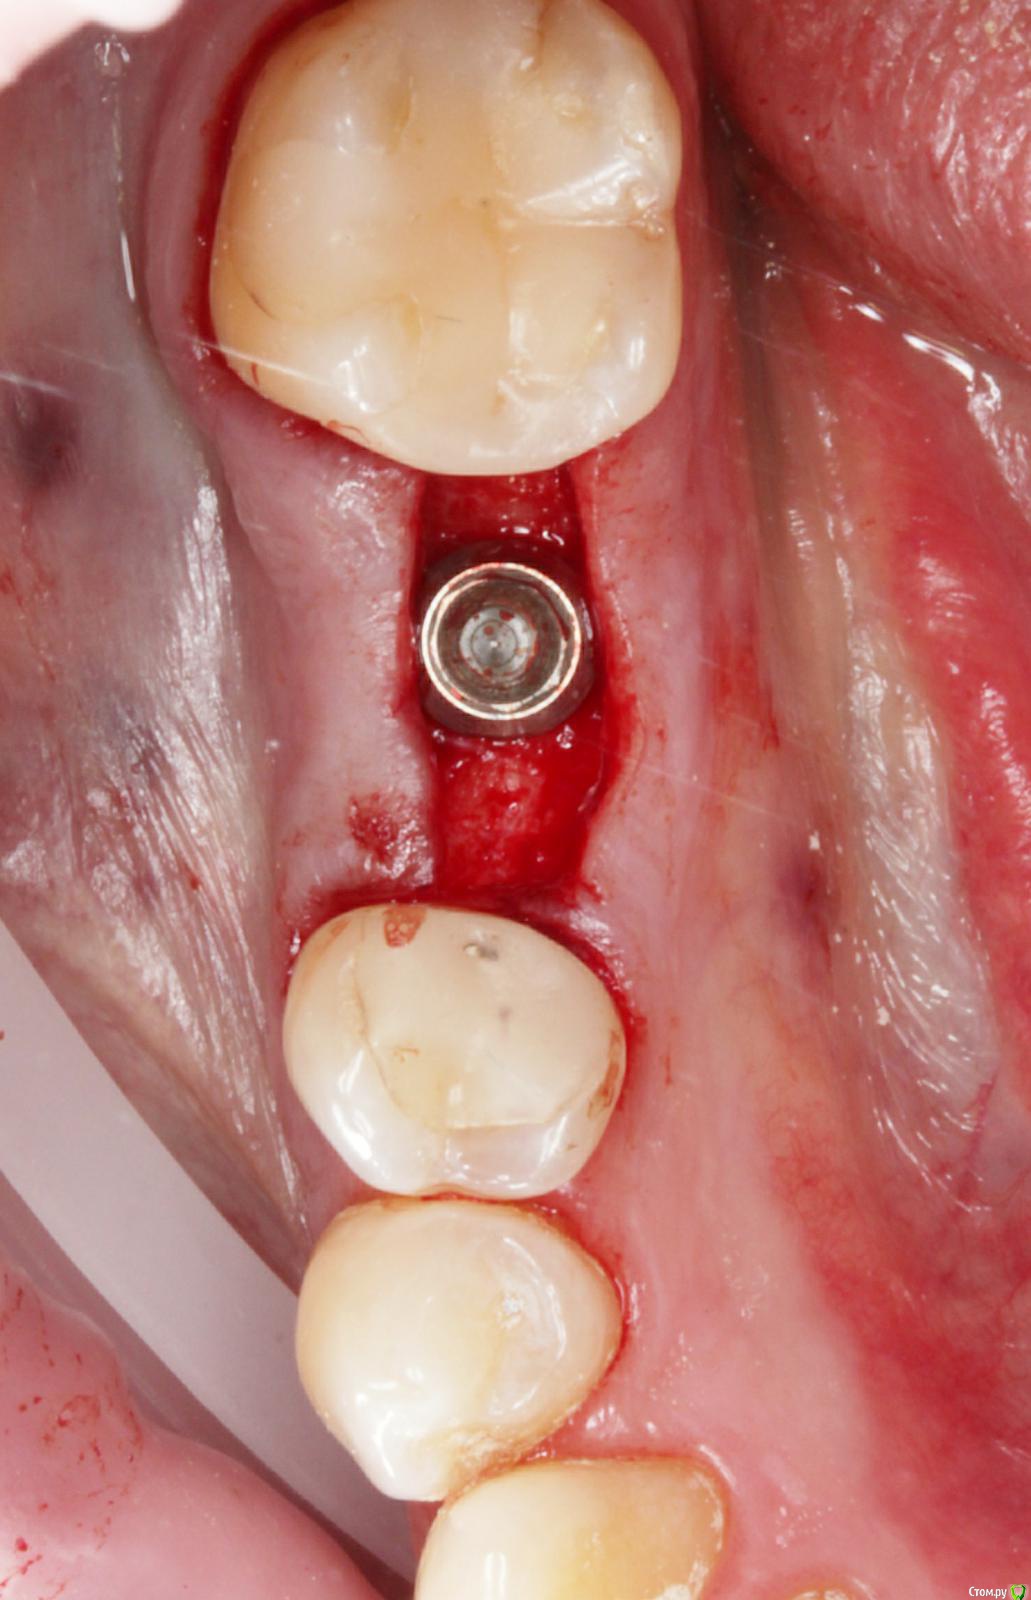

annda Опубликовано 16 сентября, 2019 Поделиться Опубликовано 16 сентября, 2019 На титановом основании сделано?Снимка нет с ортопедической работой? Ссылка на комментарий

Dmitry DK Опубликовано 18 сентября, 2019 Автор Поделиться Опубликовано 18 сентября, 2019 Да.Снимок скину На титановом основании сделано?Снимка нет с ортопедической работой? Ссылка на комментарий

Dmitry DK Опубликовано 18 сентября, 2019 Автор Поделиться Опубликовано 18 сентября, 2019 какая фиксация?Винтовая 1 Ссылка на комментарий